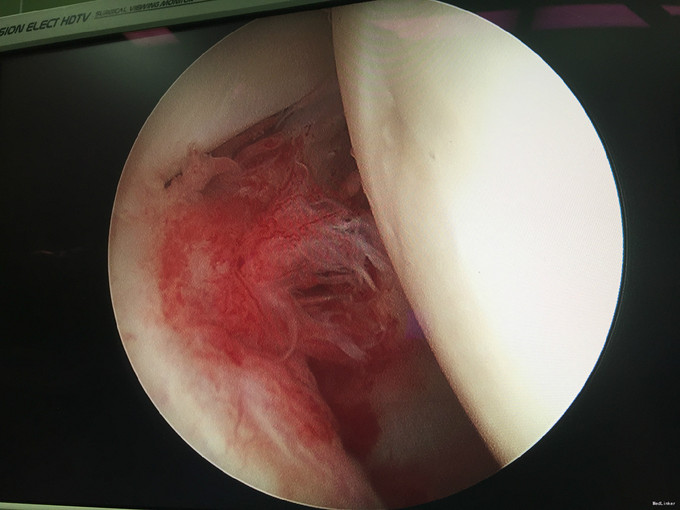

入院诊断:右肩峰下撞击综合症、右肩峰占位 治疗:右肩关节镜下肩峰成形,占位切除术

随访:患者术后感觉症状明显好转,肩关节活动度也较前改善。 讨论:该肿块性质尚无定论,仍需较长期的随访观察。请问各位专家,就目前的病史资料如何考虑该占位性质?